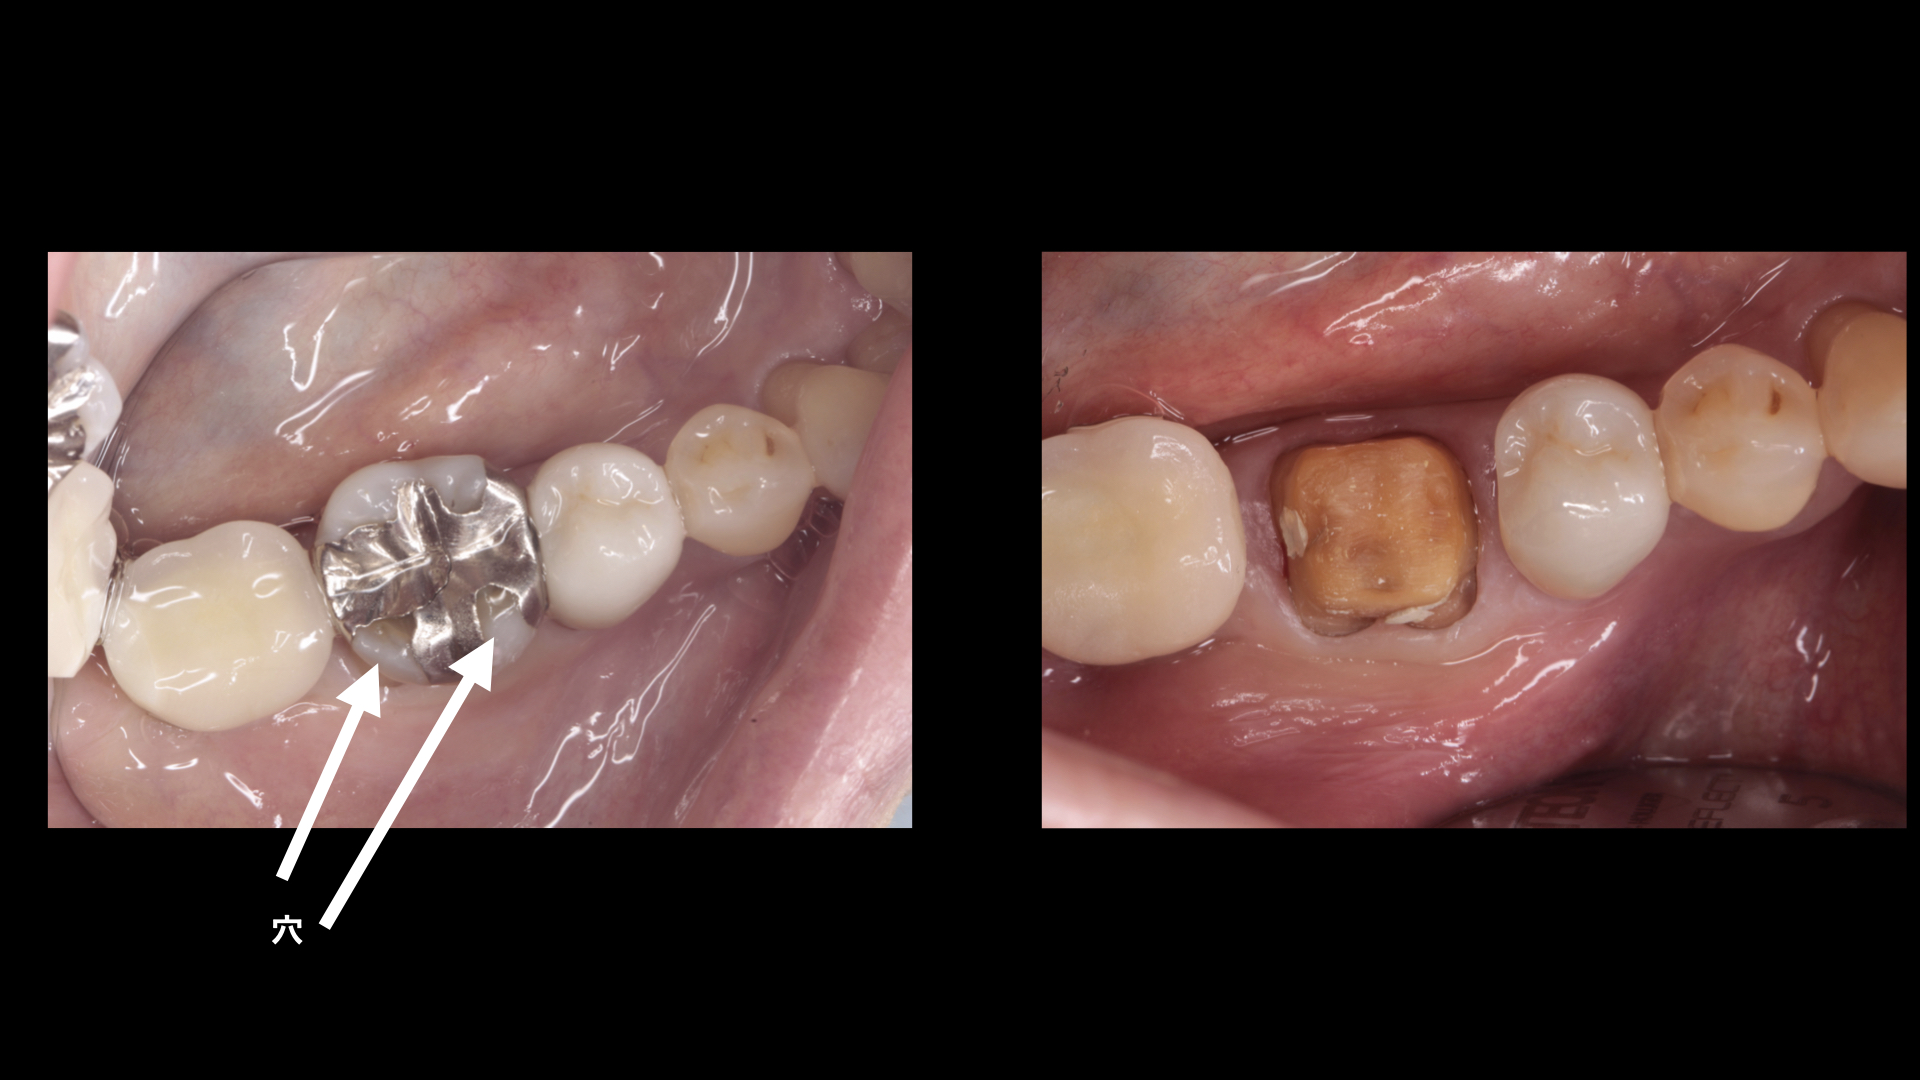

銀歯の劣化による二次カリエス治療とセラミック治療の症例 港区浜松町 大西歯科モノレールビルクリニック